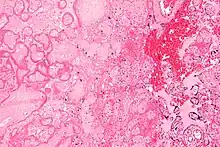

| Micrograph of a placental infarct. H&E stain. | |

A placental infarction results from the interruption of blood supply to a part of the placenta, causing its cells to die.

Small placental infarcts, especially at the edge of the placental disc, are considered to be normal at term. Large placental infarcts are associated with vascular abnormalities, e.g. hypertrophic decidual vasculopathy, as seen in hypertension.[1] Very large infarcts lead to placental insufficiency and may result in fetal death.

Maternal floor infarcts are not considered to be true placental infarcts, as they result from deposition of fibrin around the chorionic villi, i.e. perivillous fibrin deposition.